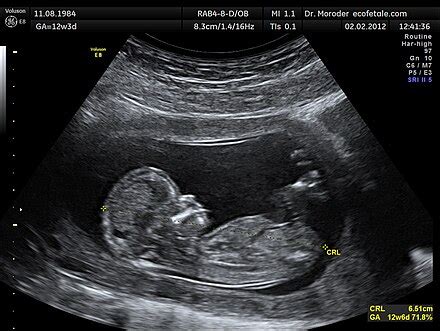

A magzatvíz, vagy orvosi nevén liquor amnii, egy tiszta, halványsárga folyadék, amely a magzatot körülvevő amnionzsákban található. A magzatvíz kettős védelmet nyújt. Elsősorban fizikai védelmet biztosít: tompítja a külső behatásokat, ütődéseket, megóvva ezzel a babát a sérülésektől. Ezen túlmenően a magzatvíz kulcsszerepet játszik a magzat fejlődésében is. Lehetővé teszi a baba számára a szabad mozgást, ami elengedhetetlen a csontok és izmok megfelelő fejlődéséhez. A magzat lenyeli a magzatvizet, ami hozzájárul a tüdők és a vesék éréséhez, valamint a tápanyagok és a hormonok keringéséhez.

Ha a kórházba érkezel a magzatvíz elfolyásának gyanújával, az egészségügyi személyzet több módszert is alkalmazhat a diagnózis megerősítésére. Az orvos vagy szülésznő steril spekulummal vizsgálja a hüvelyt és a méhnyakat. Ha a magzatvíz folyik, az látható lesz a méhnyakból vagy a hüvelyi boltozatból. Gyors és egyszerű pH-teszt is végezhető, valamint a folyadék mikroszkópos vizsgálata, amely a magzatvízben lévő sók jellegzetes, páfránylevélre emlékeztető kristályos mintázatát mutatja. Az ultrahangos vizsgálat segíthet a magzatvíz mennyiségének felmérésében (Amniotic Fluid Index - AFI).

A magzatvíz mennyisége a várandósság ideje alatt folyamatosan növekszik, a harmadik trimeszter környékén (38-39. héten) már képes elérni az 1000-1500 ml-t is, azaz az 1-1,5 liter körüli értéket.